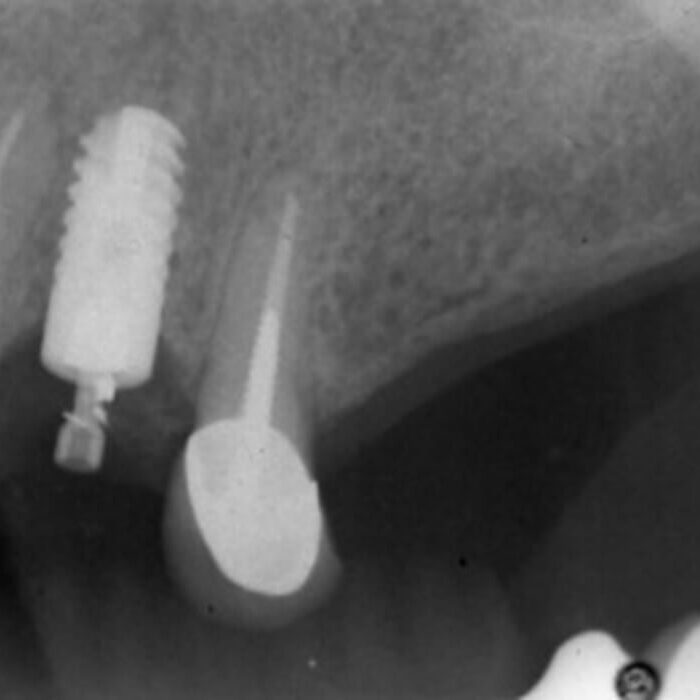

ULTRASONICS: Complications of Abutment Screw Retrieval Secondary to Prior Ultrasonic Attempts

There has been much written on the use of ultrasonics in retrieving fractured screw fragments, which I didn’t think a lot about until May of 2023, as it has not been a part of my fractured screw retrieval algorithm.